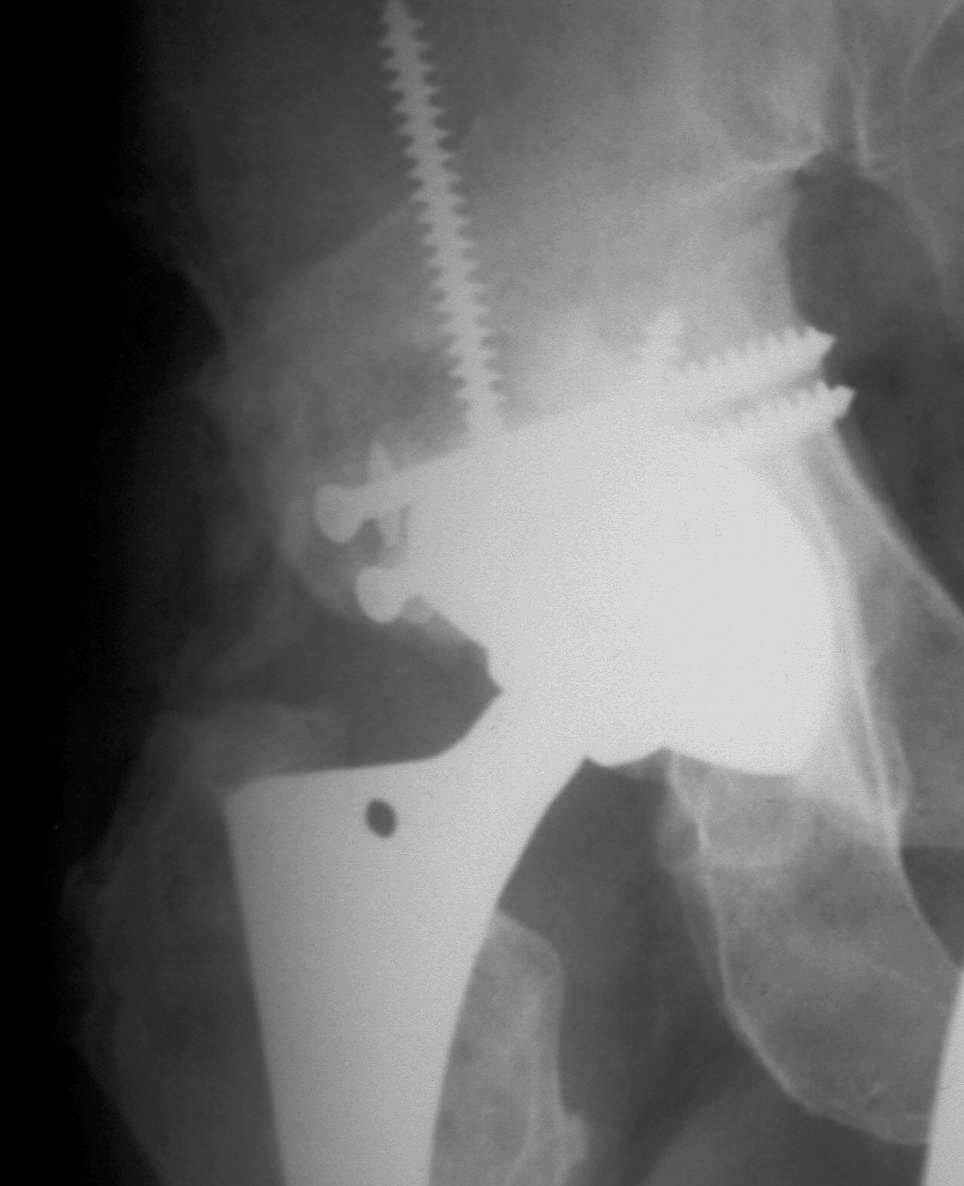

В институте совместно с фирмой Зиммер достаточно регулярно (практически ежемесячно) проводятся 2-х недельные циклы по различным вопросам эндопротезирования. Если есть возможность и желание, мы готовы поделиться с Вами нашим опытом, тем более есть что показать и что обсудить - в настоящее время ежедневно выполняется от 6 до 10 эндопротезирований коленного и тазобедренного сустава. В качестве примеров хочу показать 2 наблюдения, через 1 год и 5 лет после операции

1 год

5 лет